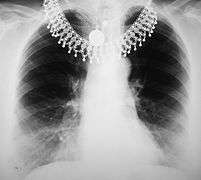

Image A: A normal chest radiograph. Image B: Q fever pneumonia.

In radiology, a chest radiograph, colloquially called a chest X-ray (CXR), or chest film, is a projection radiograph of the chest used to diagnose conditions affecting the chest, its contents, and nearby structures. Chest radiographs are the most common film taken in medicine.